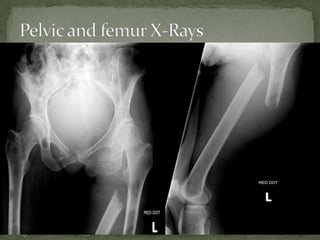

 Pt hasmetastatic breast cancer.  Note the lytic lesion on the fracture site.

 Pt hasmetastatic breast cancer.  Note the multiple lytic lesions.